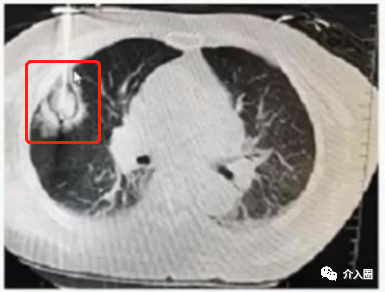

患者信息:肺轉(zhuǎn)移癌

治療方案及過程:康博刀單根消融針,消融范圍達腫瘤外緣1cm

治療結果:復查顯示病灶條索狀改變,基本消失。

▲圖5 術前